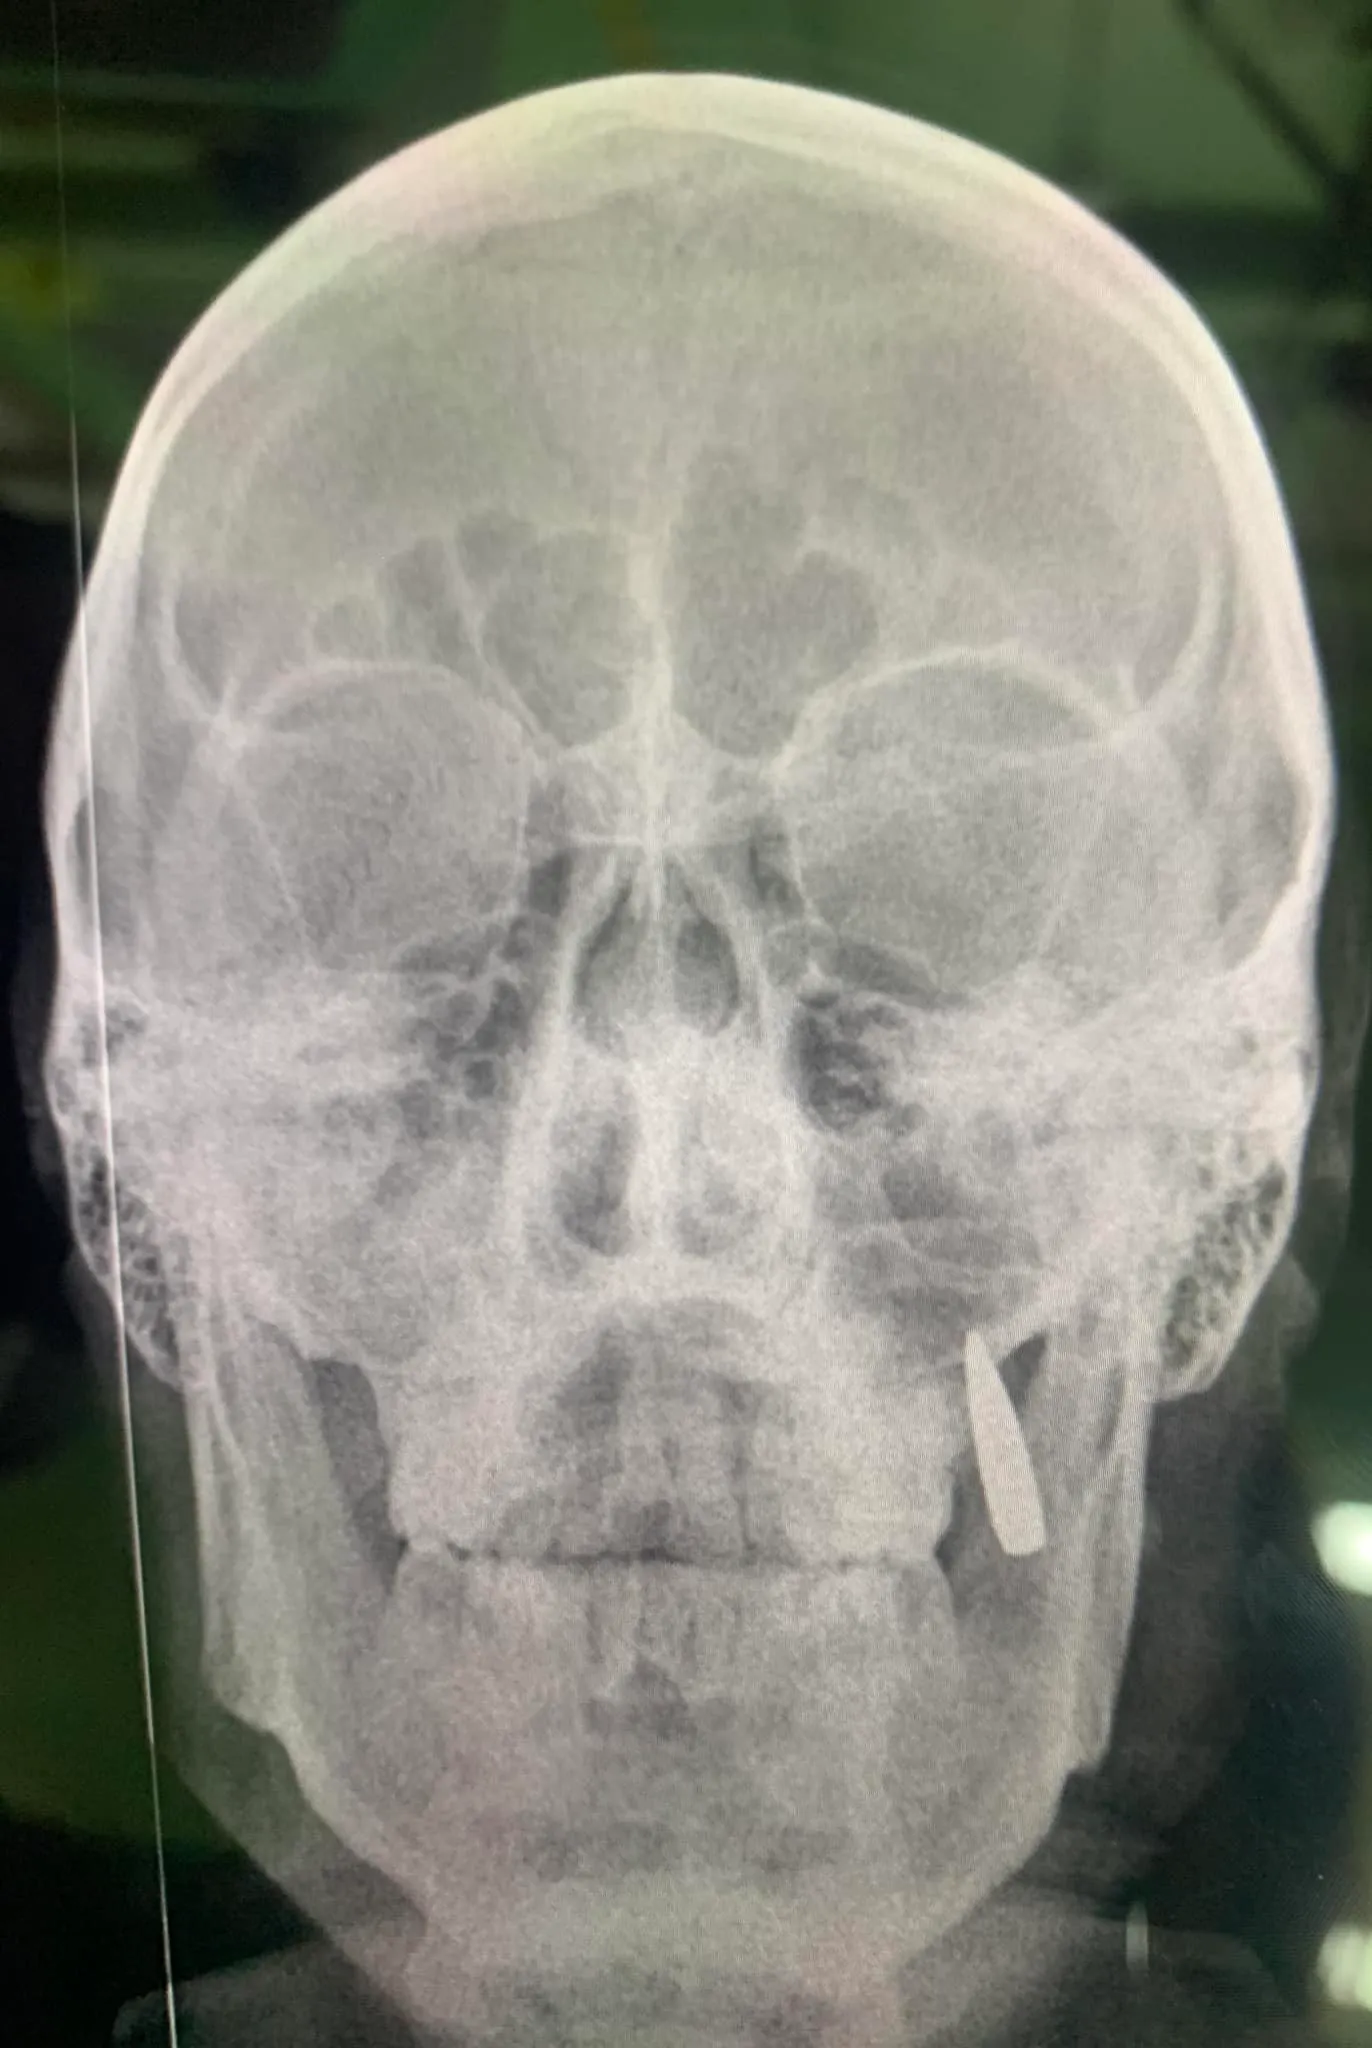

Как сообщает телеграм-канал "Новина", еще один военный поделился схожей информацией и предоставил соответствующие фото.

По словам бойца, он получил ранение еще 10 февраля. Тогда пуля вошла ему в шею с левой стороны. Правда, к счастью, не пробила насквозь, а задела хрящи и остановилась с правой стороны у челюсти.

Другой случай пули в челюсти у воина ВСУ / Фото телеграм-канала "Новина"